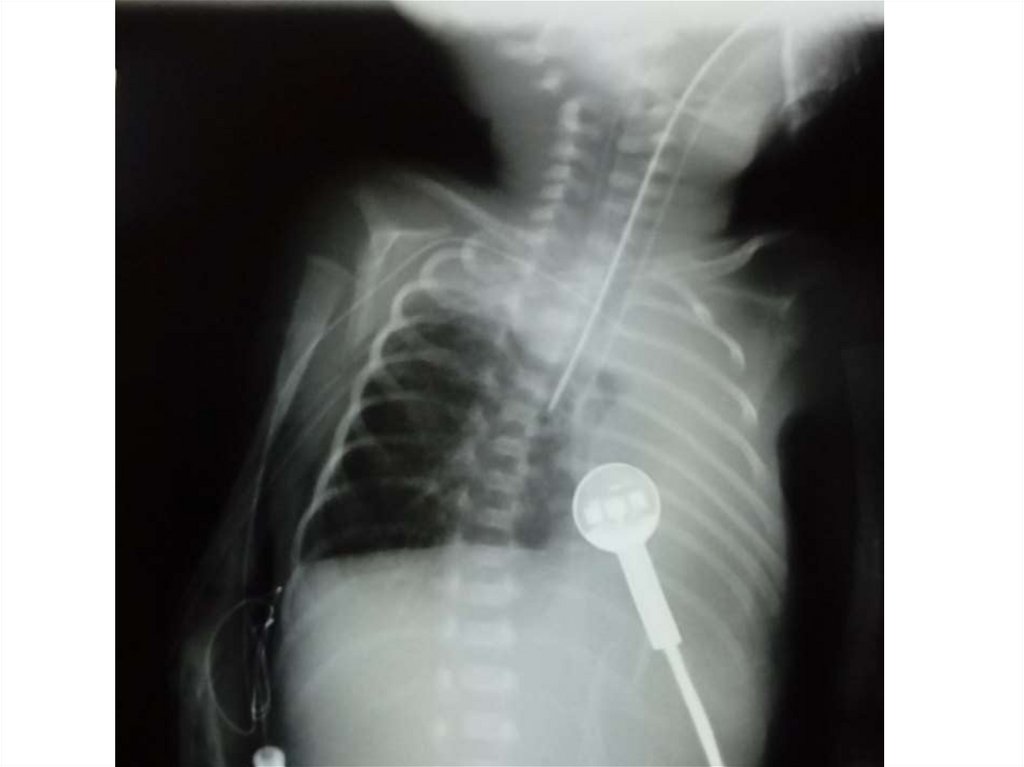

Абсцесс